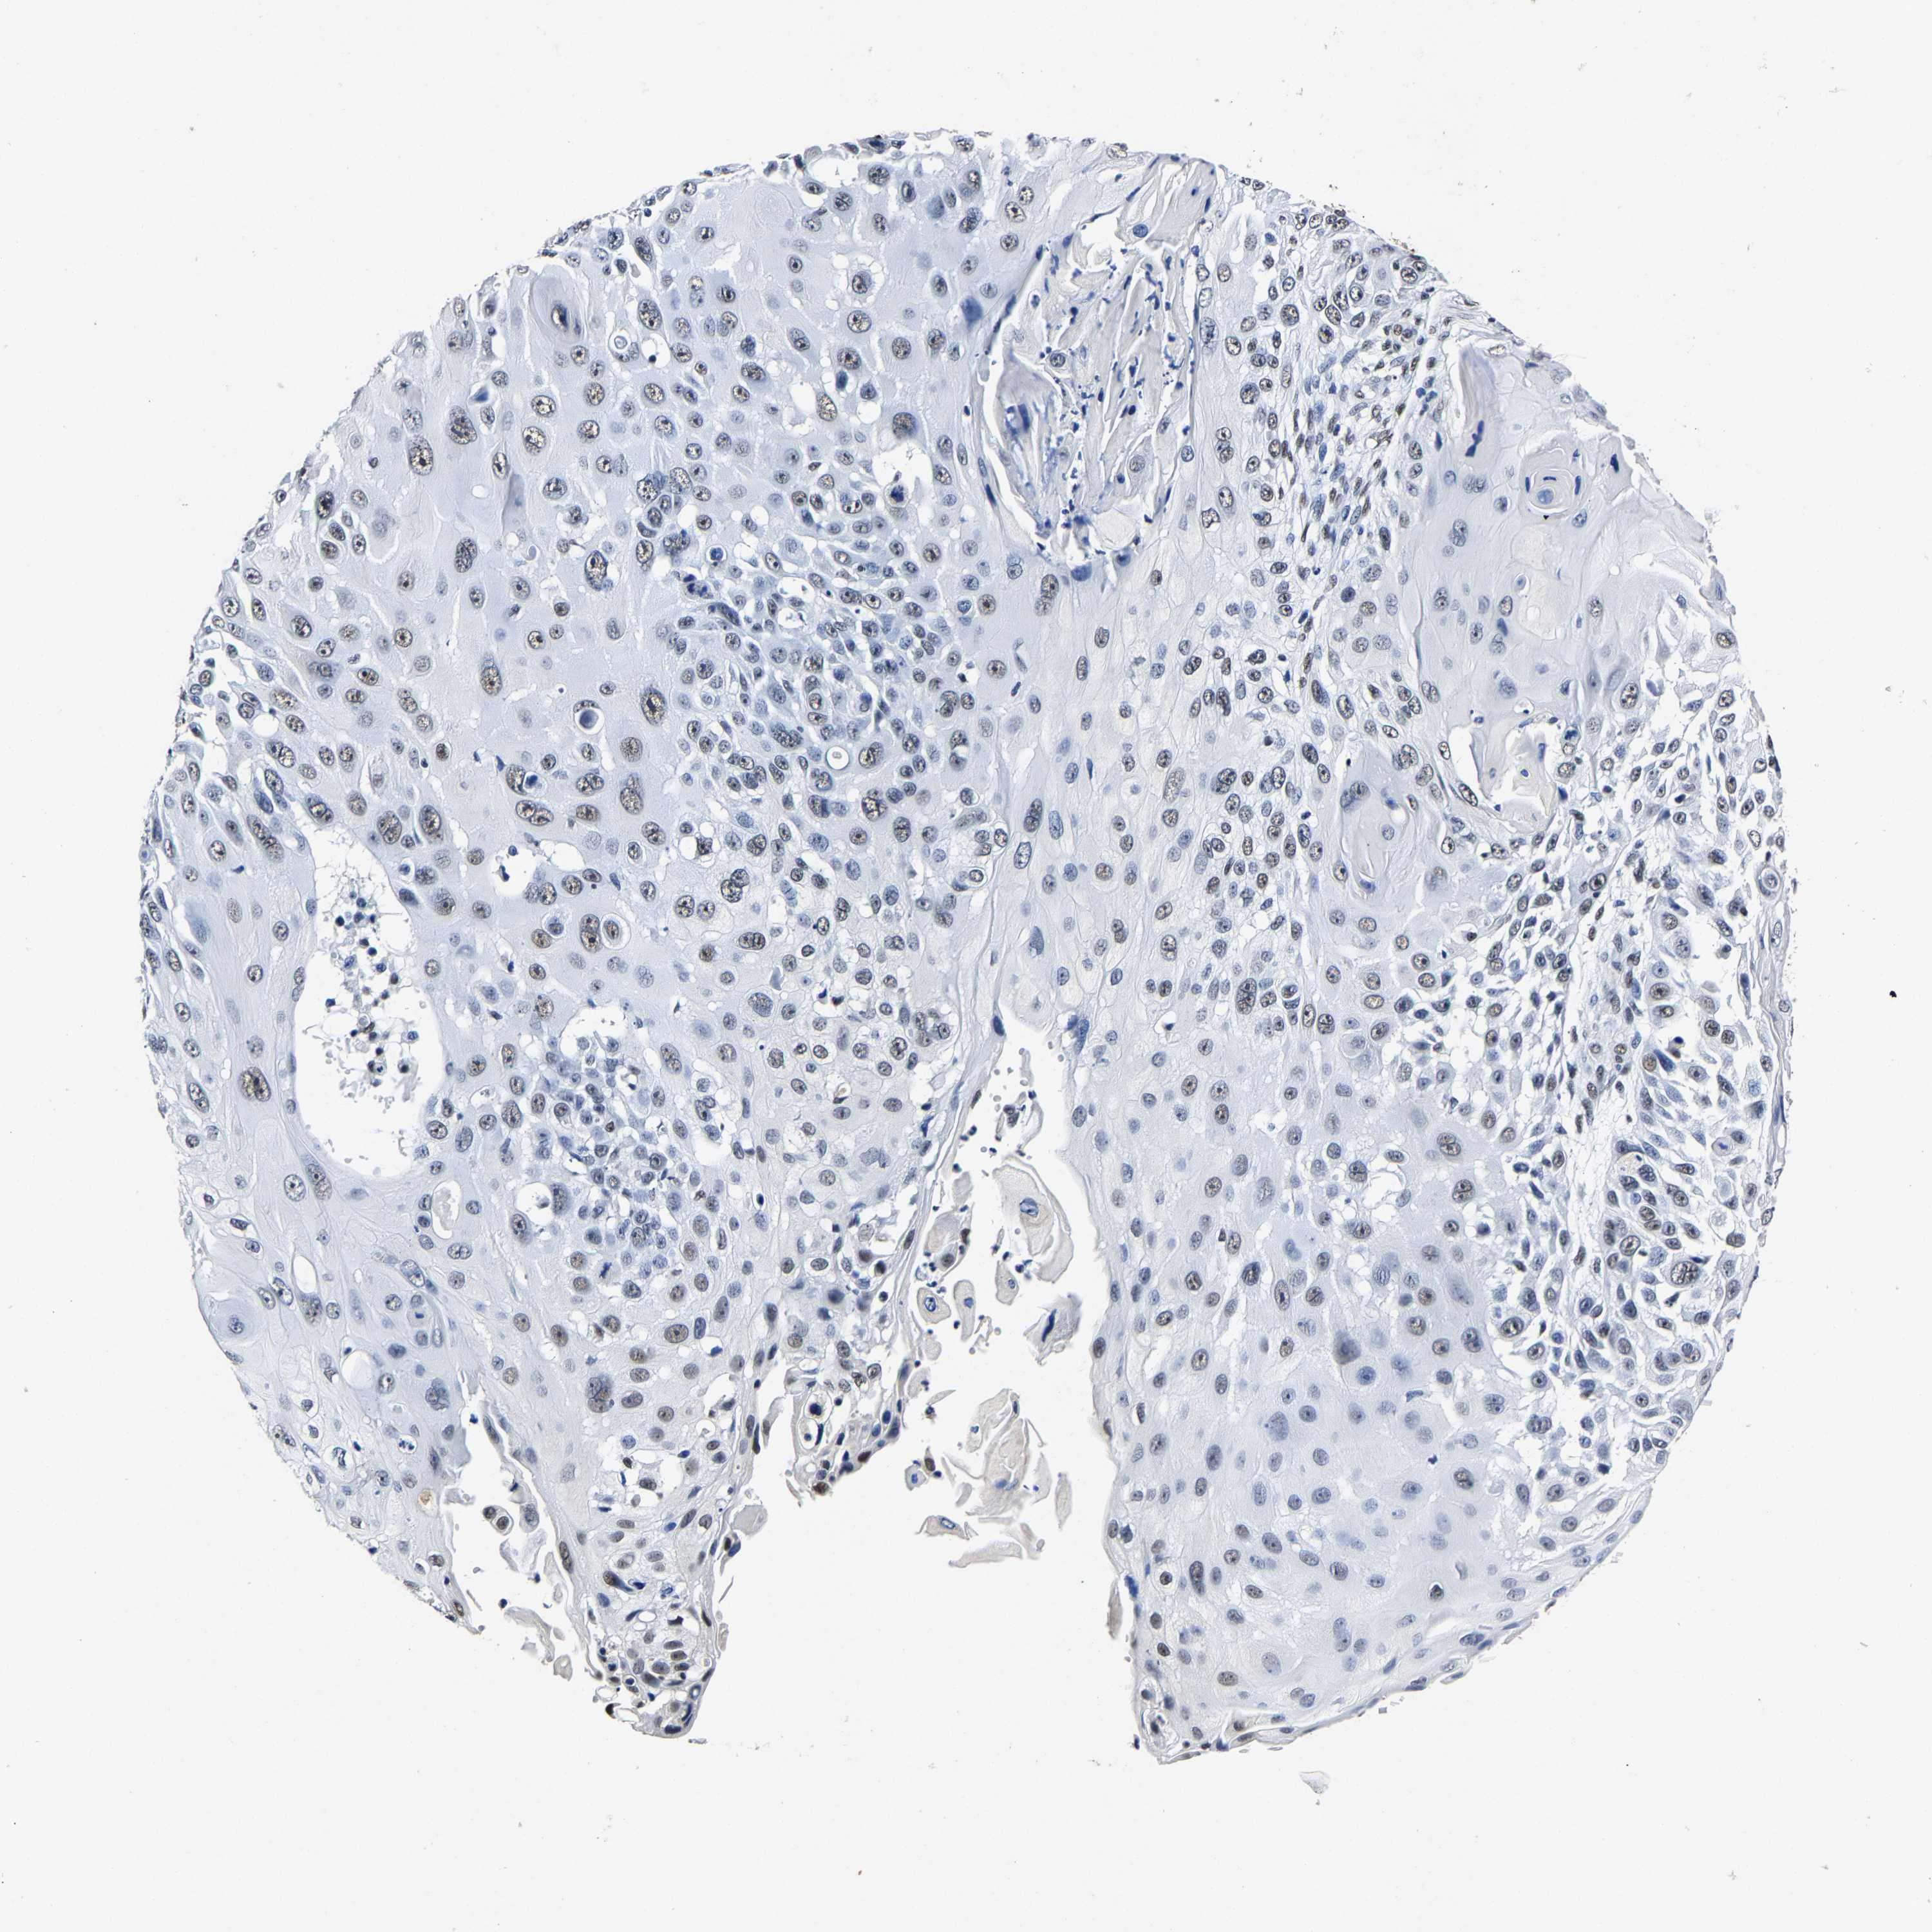

CANCER SKIN CANCER Show tissue menu

Basal cell and squamous cell cancer

SKIN CANCER - Protein expressioni

Antibody HPA020448

Staining

Medium

Intensity

Weak

Quantity

<25%

Location

None

Squamous cell carcinoma, NOS